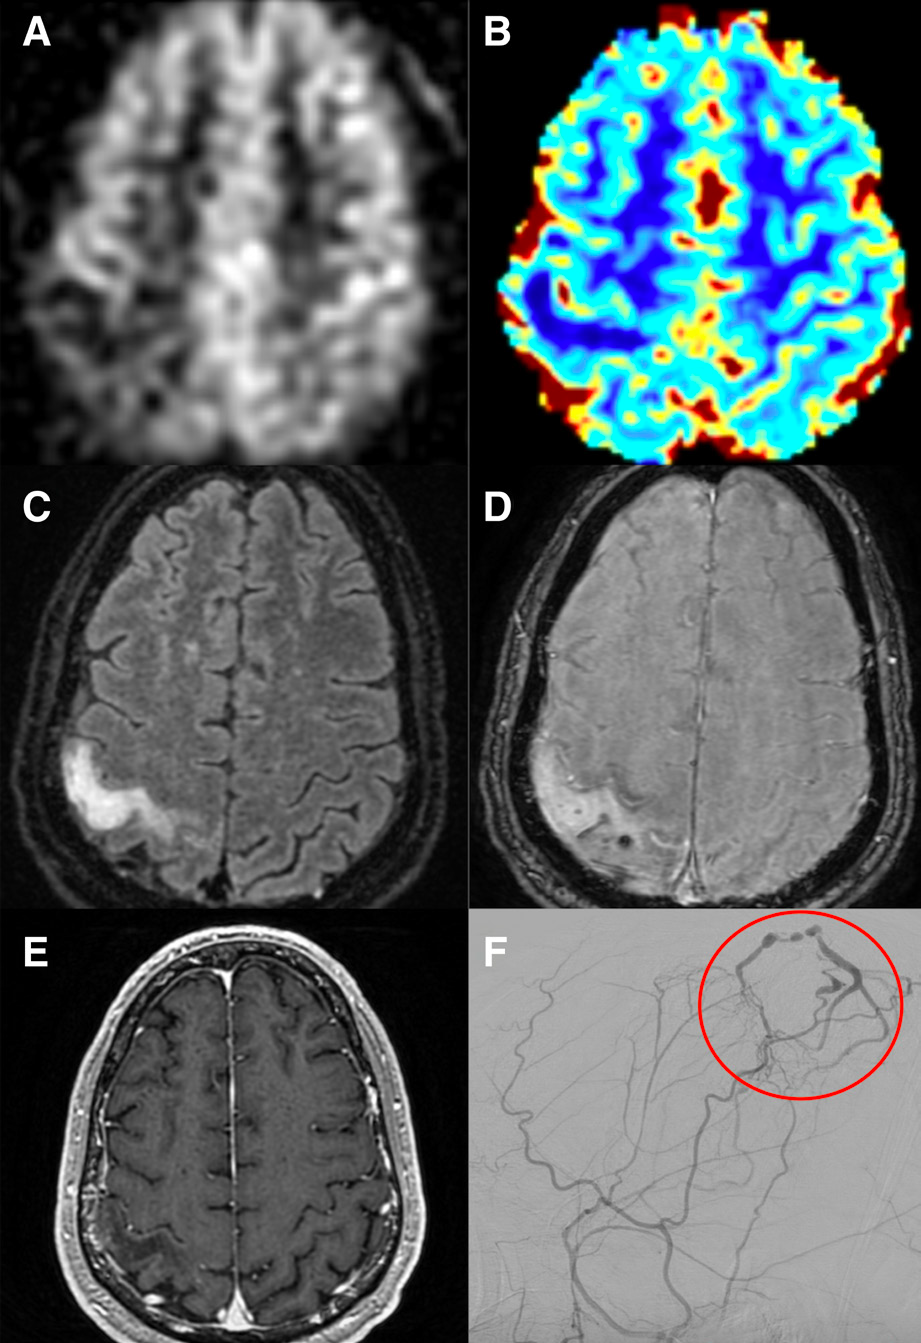

脑磁共振成像显示右侧中央后回水肿,伴有微出血和ASL(arterialspin- labeling)信号降低(图)。DSA显示右顶叶Cognard Ⅳ级硬脑膜动静脉瘘,经显微外科手术成功切除。

ASL是一种无造影剂的灌注成像。硬脑膜动静脉瘘的ASL往往表现脑血流量增加,这是动静脉分流的一个敏感和特异的迹象。本例患者的硬脑膜动静脉在ASL表现为低脑血流量。这种罕见表现可能是脑实质的血管盗血所致,先前在动静脉畸形中有描述。